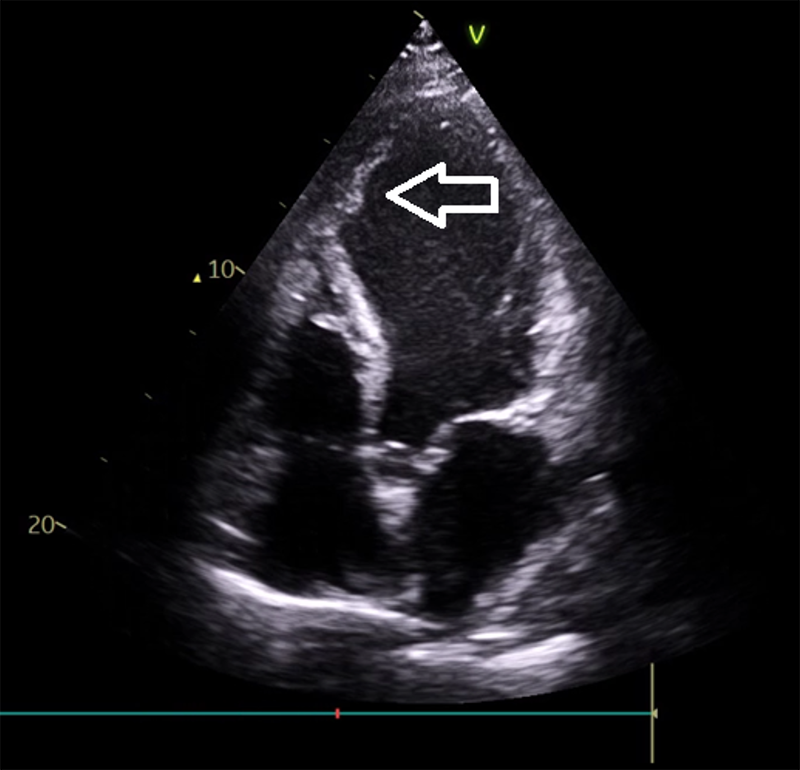

A patient in their thirties presented with chest pain, palpitations, and syncope, found to be in slow VT (figure 1). Past medical history included a late presenting large anterior wall myocardial infarction (MI) six months prior, heart failure with left ventricular ejection fraction (LVEF) 25%, left ventricular (LV) thrombus previously managed with apixaban, and a primary prevention implantable cardioverter-defibrillator (ICD). Multiple anti-arrhythmic agents, including beta blockers, amiodarone and lidocaine, failed, either due to side effects or lack of efficacy. Oral mexiletine was considered, but not used as intravenous lidocaine was not effective. ATP via the implanted ICD only very briefly restored sinus rhythm and was ineffective. Due to the presence of a large LV thrombus (figures 2 and 3) and, therefore, risk of stroke, synchronised cardioversion and acute VT ablation were not attempted. Laboratory work-up was entirely normal. This case highlights the challenges of managing refractory VT in a young patient with structural heart disease and limited procedural options.

In this patient, refractory VT persisted despite multiple antiarrhythmic therapies. The presence of a LV thrombus precluded catheter ablation as a treatment option, despite its organised appearance. The electrophysiology team advised against ablation due to the significant risk of thromboembolic complications, including stroke. Although cardioversion was recognised as carrying a high embolic risk given the well-formed thrombus, it remained a potential consideration in the event of clinical deterioration. Finally, combination therapy with high-dose bisoprolol and sotalol was utilised as a final attempt at medical therapy. This unusual combination proved to be efficacious and permitted safe discharge for a review at a specialist cardiac centre. As a result, heart transplantation was no longer considered following resolution of VT with this dual beta blocker therapy.